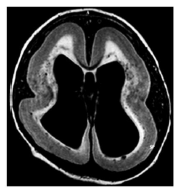

Paciente, 67 anos, hipertenso prévio, dá entrada no pronto atendimento com quadro súbito de hemiparesia esquerda, com a tomografia ilustrada na figura acima, e PA de 180x120 mmHg. Diante do quadro é correto afirmar que: